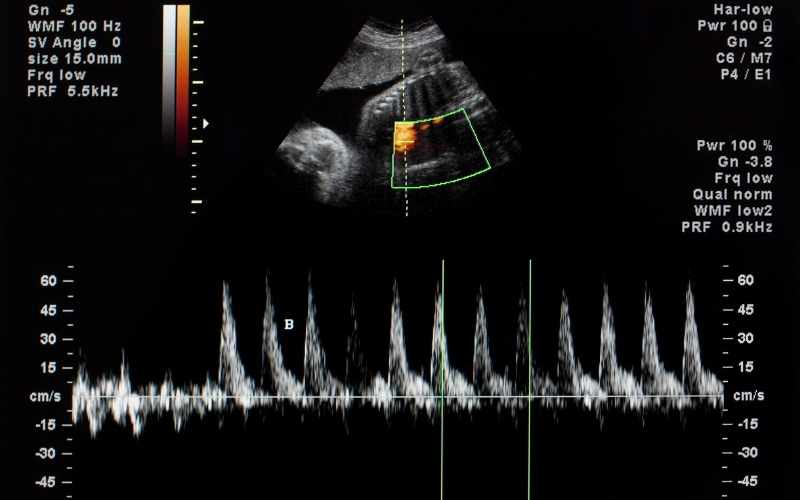

Các chuyên gia cho biết, ở giai đoạn 10 tuần của thai kỳ, tim thai vẫn còn đập rất nhẹ, chỉ dao động ở mức 140 - 170 nhịp/phút. Nếu mẹ bầu đi siêu âm đo nhịp tim của con nằm trong khoảng này thì không cần lo lắng, con vẫn phát triển bình thường.

Tuy nhiên, nếu nhịp tim thai nhi quá thấp hoặc đập quá nhanh đều rất nguy hiểm, cảnh báo nguy cơ sảy thai rất cao. Cụ thể:

Nhịp tim thai dưới 120 nhịp/phút: nguy cơ sảy thai khoảng 50%.

Nhịp tim thai dưới 90 nhịp/phút: nguy cơ sảy thai khoảng 86%.

Nhịp tim thai dưới 70 nhịp/phút: nguy cơ sảy thai khoảng 100%.

Nhịp tim thai nhanh hơn 180 nhịp/phút: thai nhi đang có vấn đề.

Đây đều là những nguyên nhân gây nguy hiểm cho cả mẹ và bé. Để đánh giá chính xác về tình trạng tim mạch của thai nhi, mẹ bầu nên tiến hành phương pháp siêu âm thai. Nếu sức khỏe thai kỳ có vấn đề, bác sĩ sẽ đưa ra biện pháp xử lý phù hợp với nguyên nhân và tuổi thai nhi.